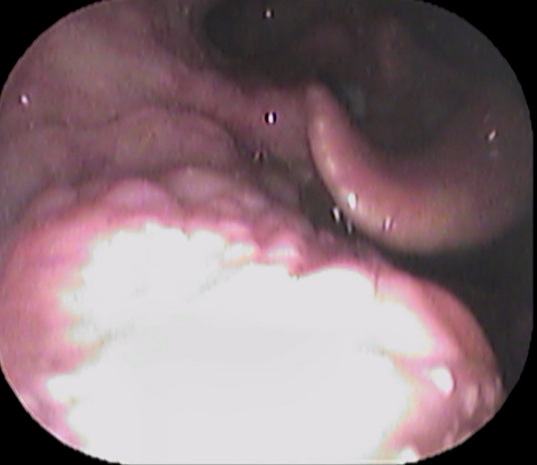

続いてファイバーで奥をチェックします

声帯の一部に白い隆起がありました。

どれかと言いますと↓

赤丸部分です。

逆流性食道炎のアンケート結果が高値で、逆流性食道炎が原因の喉頭肉芽腫と診断しました。

喉頭肉芽腫とは、慢性的な刺激が原因で声帯の後方の粘膜が炎症を起こし、白く隆起する疾患です。

逆流性食道炎が原因で声帯後方の粘膜が白く隆起したと考えられます。

逆流性食道炎の治療薬で、白い隆起は縮小していきました。